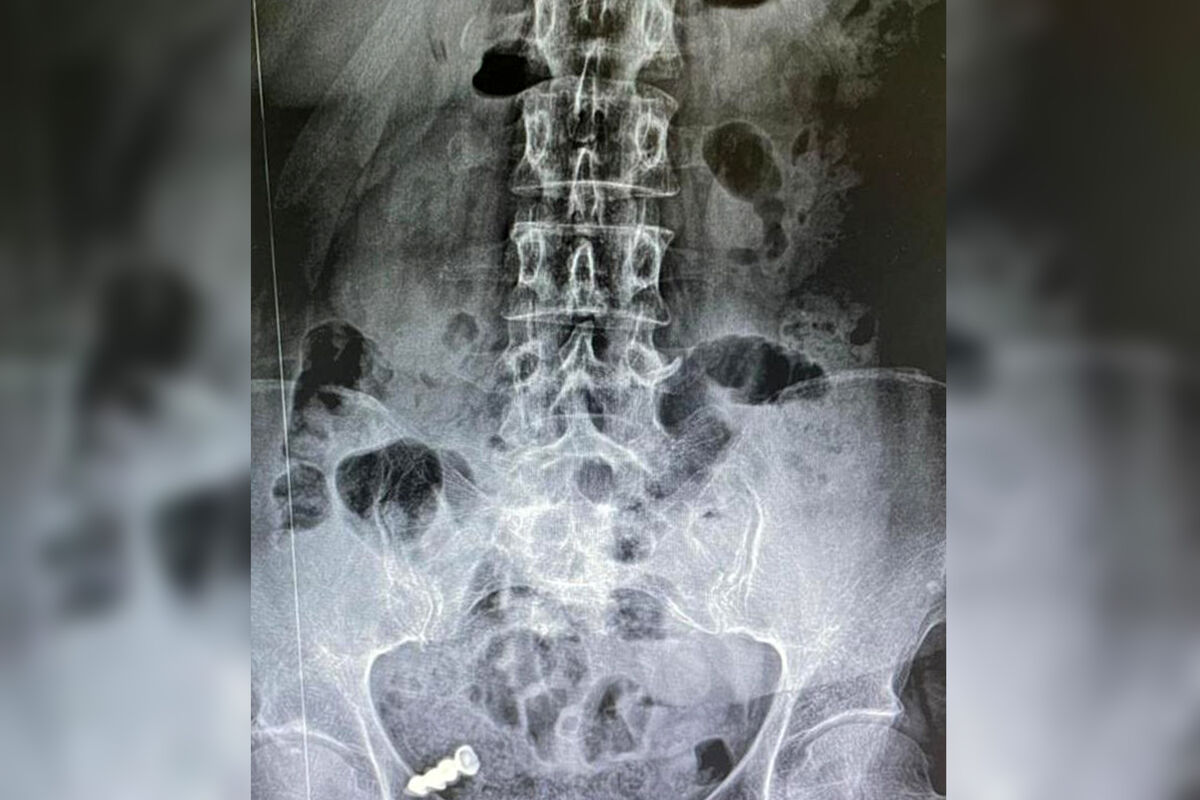

В Ростовской области врачи спасли женщину с протезом в желудке. Об этом сообщает минздрав региона.

Пациентка не сняла искусственные зубы перед сном, и, проснувшись, почувствовала недомогание.

«Утром она почувствовала неприятные ощущения в желудке и с ужасом поняла, что уснула с протезом, но сейчас его нет», – поделились в ведомстве.

Во время обследования выяснилось, что женщина проглотила протез, к этому моменту он уже находился в тонком кишечнике. Медики предположили, что инородный предмет сможет выйти естественным путем, но спустя десять дней выяснилось, что он все еще в кишечнике.

Пациентку еще раз обследовали уже в другом медучреждении и выяснили, что протез застрял в петлях тонкой кишки. Специалисты открепили мост с искусственными зубами от слизистой и провели его по кишечнику. В результате предмет извлекли. Этот случай представители минздрава назвали необычным.